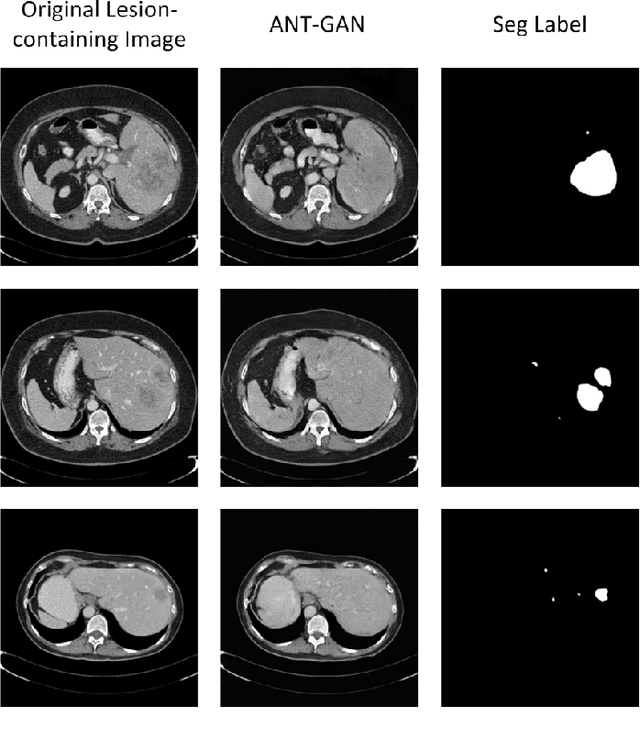

Abstract:The analysis of lesion within medical image data is desirable for efficient disease diagnosis, treatment and prognosis. The common lesion analysis tasks like segmentation and classification are mainly based on supervised learning with well-paired image-level or voxel-level labels. However, labeling the lesion in medical images is laborious requiring highly specialized knowledge. Inspired by the fact that radiologists make diagnoses based on expert knowledge on "healthiness" and "unhealthiness" developed from extensive experience, we propose an medical image synthesis model named abnormal-to-normal translation generative adversarial network (ANT-GAN) to predict a normal-looking medical image based on its abnormal-looking counterpart without the need of paired data for training. Unlike typical GANs, whose aim is to generate realistic samples with variations, our more restrictive model aims at producing the underlying normal-looking image corresponding to an image containing lesions, and thus requires a specialized design. With an ability to segment normal from abnormal tissue, our model is able to generate a highly realistic lesion-free medical image based on its true lesion-containing counterpart. Being able to provide a "normal" version of a medical image (possibly the same image if there is no illness) is not only an intriguing topic, but also can serve as a pre-processing and provide useful side information for medical imaging tasks like lesion segmentation or classification validated by our experiments.